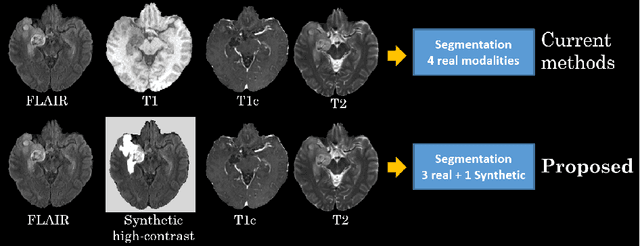

Abstract:Magnetic resonance imaging (MRI) provides varying tissue contrast images of internal organs based on a strong magnetic field. Despite the non-invasive advantage of MRI in frequent imaging, the low contrast MR images in the target area make tissue segmentation a challenging problem. This paper demonstrates the potential benefits of image-to-image translation techniques to generate synthetic high tissue contrast (HTC) images. Notably, we adopt a new cycle generative adversarial network (CycleGAN) with an attention mechanism to increase the contrast within underlying tissues. The attention block, as well as training on HTC images, guides our model to converge on certain tissues. To increase the resolution of HTC images, we employ multi-stage architecture to focus on one particular tissue as a foreground and filter out the irrelevant background in each stage. This multi-stage structure also alleviates the common artifacts of the synthetic images by decreasing the gap between source and target domains. We show the application of our method for synthesizing HTC images on brain MR scans, including glioma tumor. We also employ HTC MR images in both the end-to-end and two-stage segmentation structure to confirm the effectiveness of these images. The experiments over three competitive segmentation baselines on BraTS 2018 dataset indicate that incorporating the synthetic HTC images in the multi-modal segmentation framework improves the average Dice scores 0.8%, 0.6%, and 0.5% on the whole tumor, tumor core, and enhancing tumor, respectively, while eliminating one real MRI sequence from the segmentation procedure.

Abstract:The magnetic resonance (MR) analysis of brain tumors is widely used for diagnosis and examination of tumor subregions. The overlapping area among the intensity distribution of healthy, enhancing, non-enhancing, and edema region makes the automatic segmentation a challenging task. Here, we show that a convolutional neural network trained on high-contrast images can transform intensity distribution of brain lesion in its internal subregions. Specifically, generative adversarial network (GAN) is extended to synthesize high-contrast images. A comparison of these synthetic images and real images of brain tumor tissue in MR scans showed significant segmentation improvement and decreased the number of real channels for segmentation. The synthetic images are used as a substitute for real channels and can bypass real modalities in the multimodal brain tumor segmentation framework. Segmentation results on BraTS 2019 dataset demonstrate that our proposed approach can efficiently segment the tumor areas.